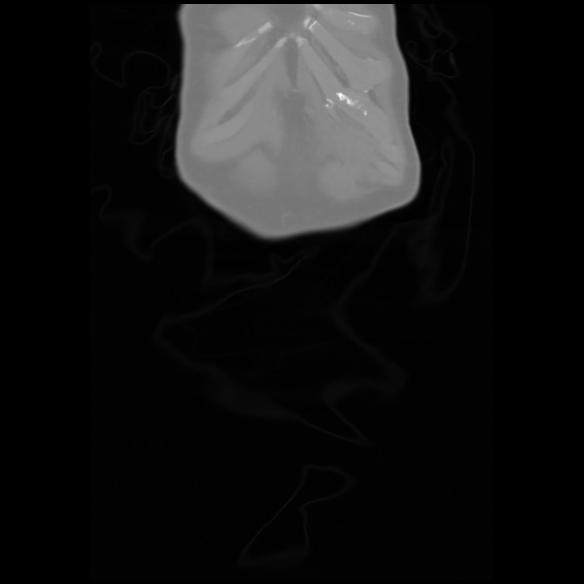

6 CUERPO,CE,Coronal,3.000,CUERPO,Coronal,